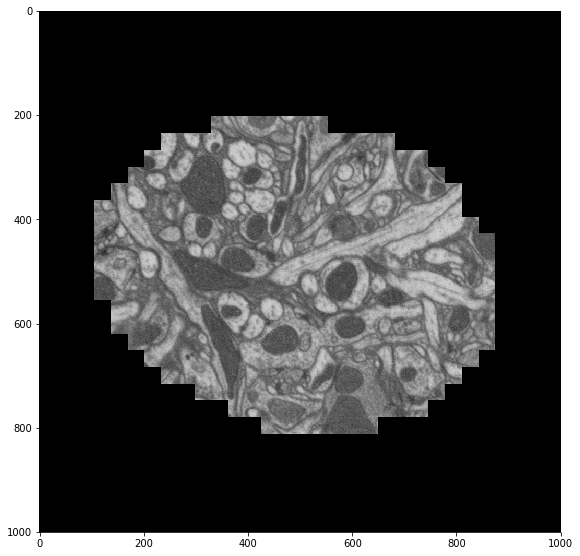

Electron microscopy may be generating the biggest ndarray datasets in the field - terabytes regularly. Neuroscience needs EM to see connections between neurons, because the critical features of neural synapses (connections) are below the diffraction limit of light microscopes. This type of research has been called “connectomics”. Many groups are looking at machine vision approaches to follow small neuron parts from one slice to the next.

This data is from drosophila: http://emdata.janelia.org/. Here is an example 2d slice of the data http://emdata.janelia.org/api/node/bf1/grayscale/raw/xy/2000_2000/1800_2300_5000.

Sample electron microscopy image from stack

The last number in the URL is an index into a large stack of about 10000 images. We can change that number to get different slices through our 3D dataset.